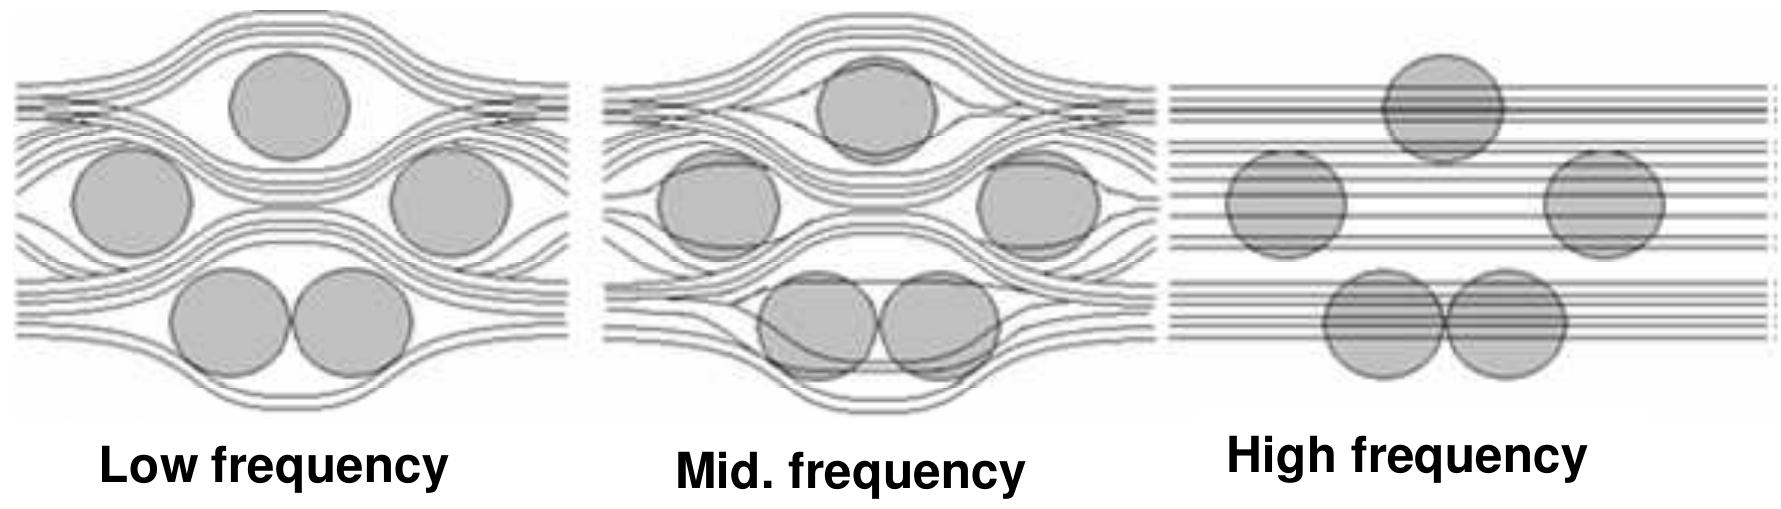

The paper examines electrophysiological activity produced by exposing the brains of laboratory animals to rectangular pulses of microwave energy. These results suggest that a microwave auditory phenomenon is evoked by a mechanism similar... more